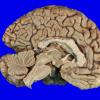

5 Parkinson's Dz (Case 5 WUMS Case) 4

5 Parkinson's Dz (Case 5) SNigra H&E 5 copy

5A1 AD & PD (Case 5) 3

5A1 DLBD (Case 5) _1

5A1 DLBDz (Case 5) H&E Cortex 5